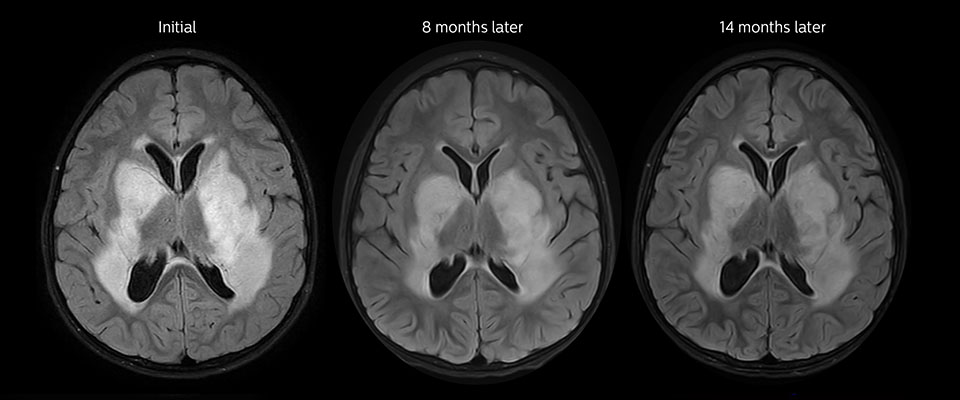

MRI may be performed after tumor resection, to look for residual tumor or tumor regrowth. Also here, the different contrast mechanism of APT may help in diagnosis. Dr. Miller remembers a particular case. “After a very good resection, we saw small changes on the postcontrast T1-weighted and the T2-weighted images that looked like a post-surgical little bit of fluid. Interestingly, however, we saw a focal area of APT signal, right in the center of that abnormality. As we usually do when a bit unsure, we followed it up and, unfortunately, found tumor regrowth in that region,” Dr. Miller says. “Cases like this motivate me, and others who care about this population, to investigate how this APT method could be used on large scale in this population and help us in providing high value diagnostic information.” The hospital’s physicians also saw a case where APT had a negative predictive value. Following the resection of a highgrade tumor, they saw a similar small change in the images of this patient. However in this case, the APT signal was rather low. In a recent rescanning of this patient, no recurrence was seen.

MRI with APT post resection

Immediately post resection MRI was again performed. T2-weighted and postcontrast T1-weighted images are quite inconclusive for distinguishing residual tumor tissue from postoperative tissue changes. On the APT image some high signal is still seen, which would suggest residual tumor tissue.

Follow-up over time

In later follow-up scans the post-contrast T1-weighted images suggest recurrent tumor growth. So, it would be interesting to study the predictive value of APT in a large patient group.